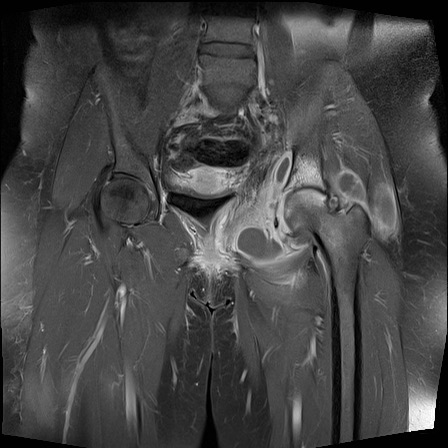

Hình ảnh X-quang khung chậu của bệnh nhân viêm khớp do lao tại khớp háng trái.

Có hẹp khe khớp kín đáo kèm theo xơ cứng dưới sụn tại khớp háng trái.

Các dấu hiệu X-quang này không đặc hiệu và rất có thể là biểu hiện của thoái hóa khớp.

Tiếp tục xem hình ảnh MRI…

Điều bất ngờ với tất cả mọi người là có nhiều ổ áp-xe.

Khi hình thành áp-xe lan rộng như vậy trong khi biểu hiện lâm sàng lại tối thiểu, cần luôn nghĩ đến viêm khớp do lao.

Chẩn đoán viêm khớp do lao được xác lập bằng chọc hút dịch khớp.